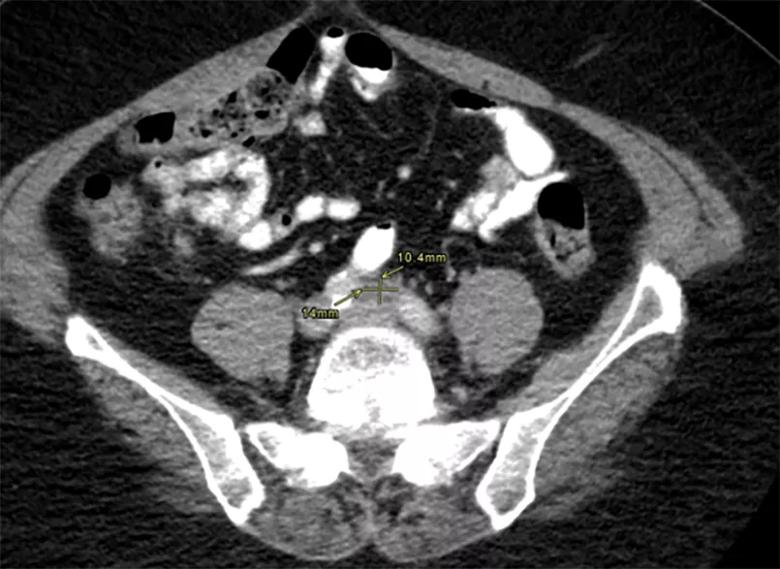

CT imaging of the patient’s chest revealed pulmonary nodules and axillary lymphadenopathy. Imaging of her abdomen revealed a 22.4 mm x 18.1 mm soft-tissue lesion between the proximal common iliac arteries, eccentric soft-tissue thickening along the left anterolateral wall of the abdominal aorta, and mild infiltration adjacent to the distal abdominal aorta, which was concerning for retroperitoneal fibrosis (Figure 3). Subtle haziness adjacent to the pancreatic tail was also seen, which raised the possibility of autoimmune pancreatitis.

xray

Figure 3. CT abdomen showing a 22.4 mm x 18.1 mm soft tissue lesion between the proximal common iliac arteries, eccentric soft tissue thickening along the left anterolateral wall of the abdominal aorta, and mild infiltration adjacent to the distal abdominal aorta concerning for retroperitoneal fibrosis.